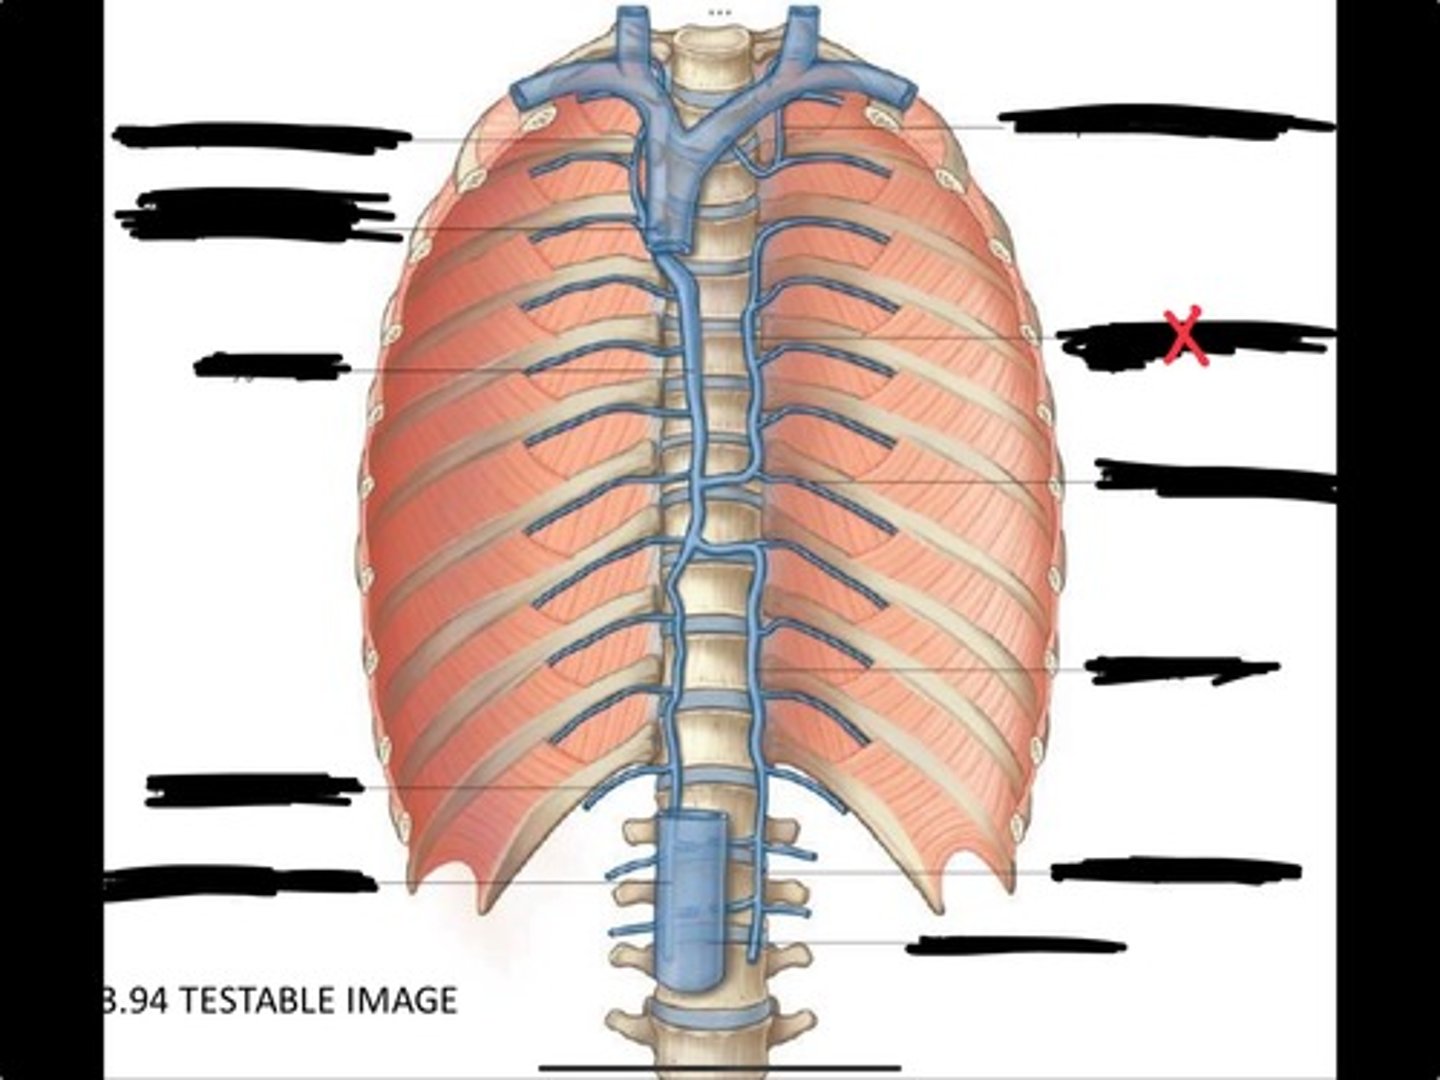

Right ascending lumbar vein

Right subcostal vein

Azygos vein

Opening of the azygos vein into superior vena cava

Right superior intercostal vein

Left superior intercostal vein

Accessory hemiazygos vein

Posterior intercostal vein

Hemiazygous vein

Ascending lumbar vein